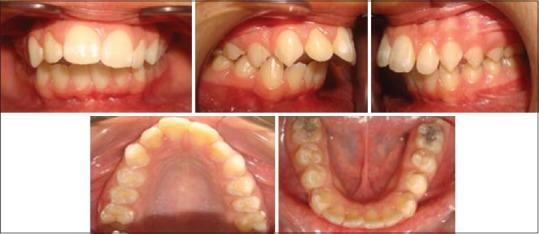

Unilateral condylar hyperplasia is an uncommon condition with unknown etiology which causes overdevelopment of condyle leading to facial asymmetry, mandibular deviation, malocclusion, and articulation dysfunction. Two Indian families with unilateral condylar hyperplasia are presented where the similar abnormality was also detected in one of their parents. The condylar hyperplasia in these two families indicates that mandibular condylar hyperplasia could be genetic in origin.

单侧髁突增生是一种病因不明的罕见病症,它会导致髁突过度发育,进而引起面部不对称、下颌偏斜、错牙合畸形及关节功能障碍。本文报告了两个患有单侧髁突增生的印度家族,在他们的一位家长中也检测到了类似异常。这两个家族中的髁突增生表明下颌髁突增生可能起源于遗传。